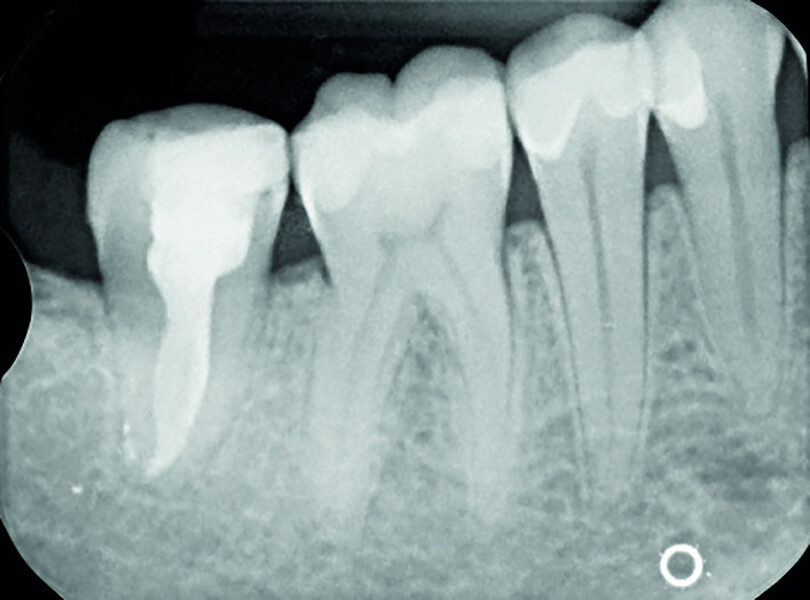

Fig. 19a: Radiographs: Pre-op periapical.

Fig. 19b: Radiographs: Immediately after transplantation.

Fig. 19c: Radiographs: One-year recall.

Fig. 19d: Radiographs: Two-year recall.